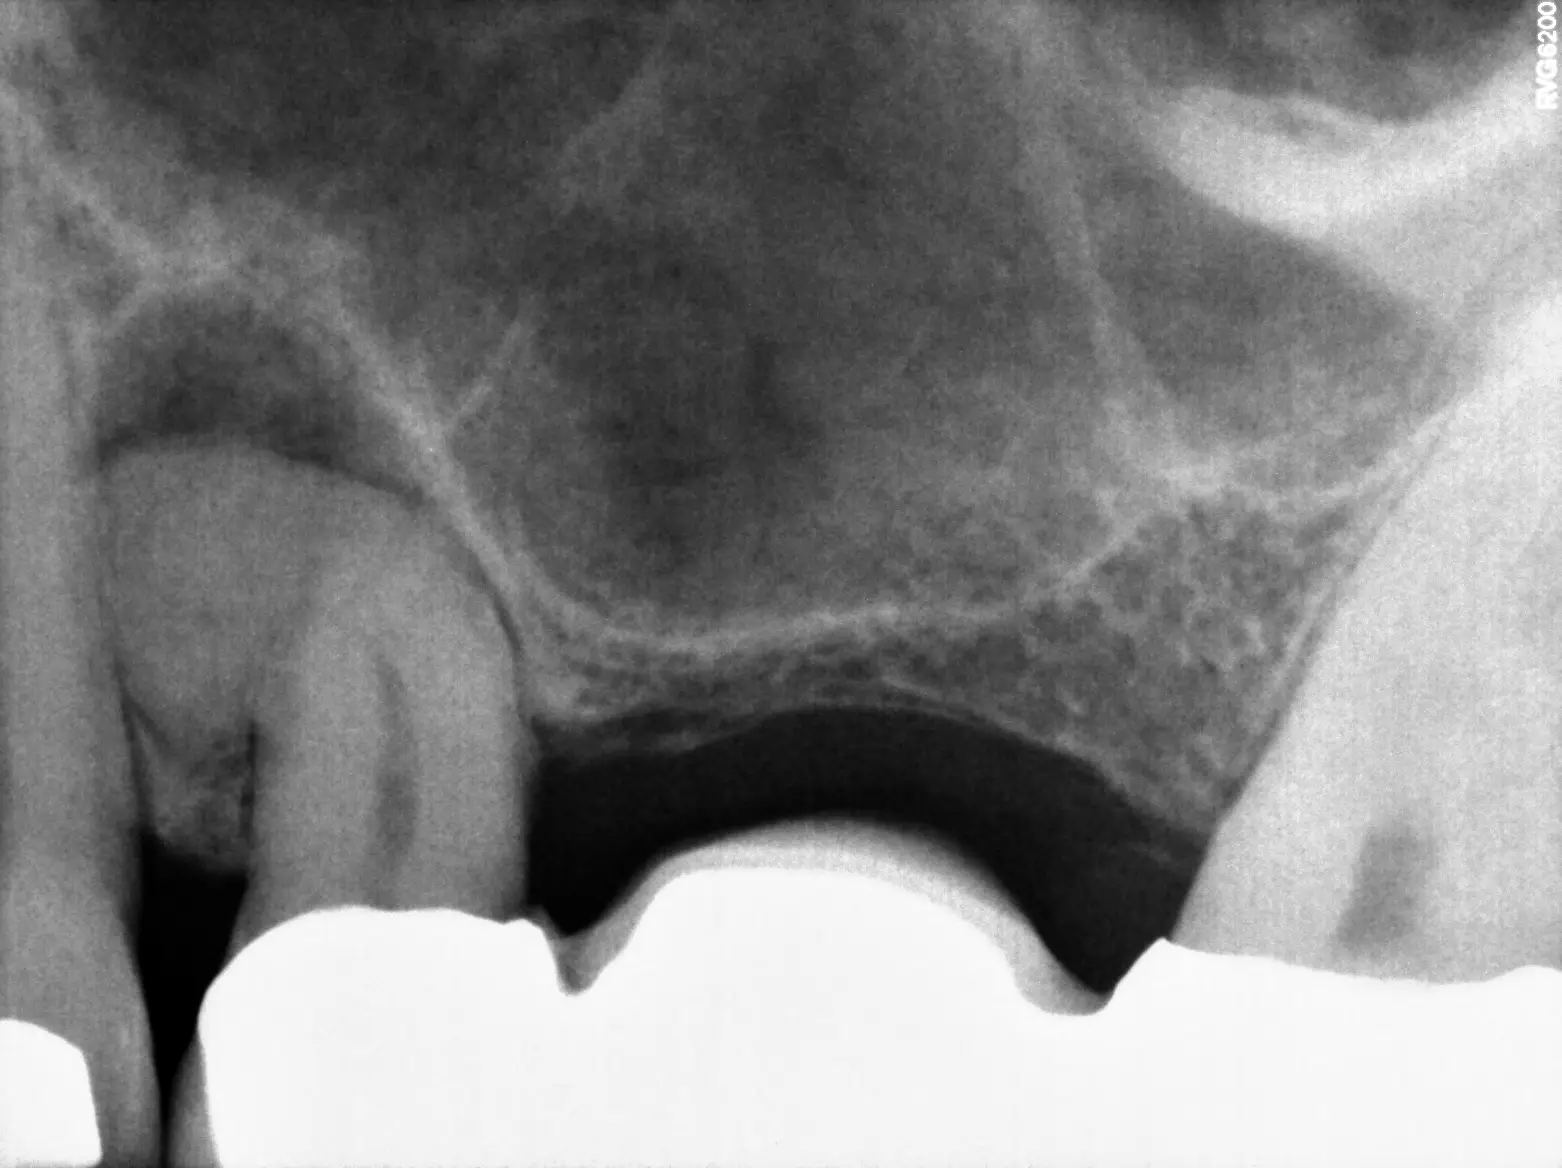

To find the source of your dental pain, your endodontist will begin by performing a comprehensive exam and review of your x-rays to get a complete picture of your oral health. If your tooth is infected, they will determine the extent of the infection to decide if root canal therapy will be an effective treatment.

Your general dentist may have already taken some recent X-rays of your teeth before your visit with us. To arrive at a diagnosis and recommend treatment, we require specific angles of the tooth that can only be obtained with in-house imaging. We will do our best to obtain the images from your referring dentist and compare them to our own, so that we can review the complete picture with you

If you have previously undergone root canal treatment and are experiencing persistent tooth pain or discomfort, it could indicate the presence of new infections, untreated canals, or other issues that need to be addressed. Thankfully, we may be able to save your tooth. Schedule a consultation with our office, and we can discuss if you’re a good candidate for either endodontic retreatment or apical surgery.